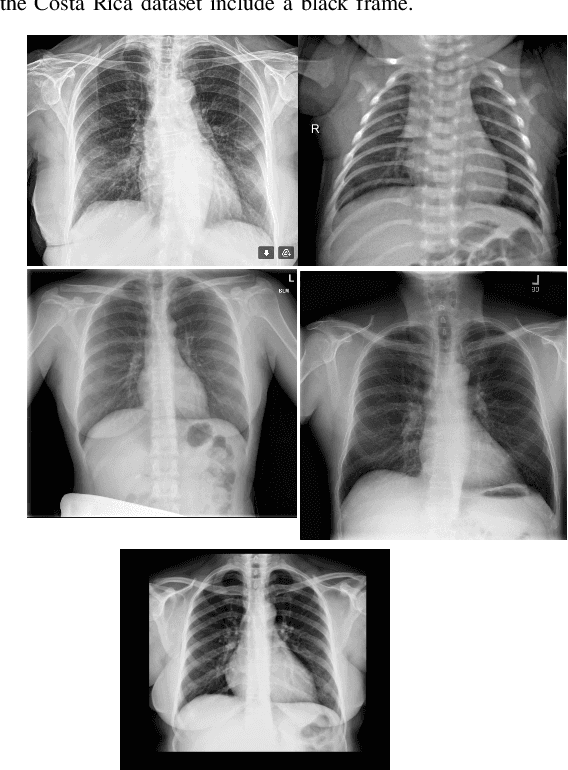

Abstract:In the context of the global coronavirus pandemic, different deep learning solutions for infected subject detection using chest X-ray images have been proposed. However, deep learning models usually need large labelled datasets to be effective. Semi-supervised deep learning is an attractive alternative, where unlabelled data is leveraged to improve the overall model's accuracy. However, in real-world usage settings, an unlabelled dataset might present a different distribution than the labelled dataset (i.e. the labelled dataset was sampled from a target clinic and the unlabelled dataset from a source clinic). This results in a distribution mismatch between the unlabelled and labelled datasets. In this work, we assess the impact of the distribution mismatch between the labelled and the unlabelled datasets, for a semi-supervised model trained with chest X-ray images, for COVID-19 detection. Under strong distribution mismatch conditions, we found an accuracy hit of almost 30\%, suggesting that the unlabelled dataset distribution has a strong influence in the behaviour of the model. Therefore, we propose a straightforward approach to diminish the impact of such distribution mismatch. Our proposed method uses a density approximation of the feature space. It is built upon the target dataset to filter out the observations in the source unlabelled dataset that might harm the accuracy of the semi-supervised model. It assumes that a small labelled source dataset is available together with a larger source unlabelled dataset. Our proposed method does not require any model training, it is simple and computationally cheap. We compare our proposed method against two popular state of the art out-of-distribution data detectors, which are also cheap and simple to implement. In our tests, our method yielded accuracy gains of up to 32\%, when compared to the previous state of the art methods.

Abstract:The implementation of deep learning based computer aided diagnosis systems for the classification of mammogram images can help in improving the accuracy, reliability, and cost of diagnosing patients. However, training a deep learning model requires a considerable amount of labeled images, which can be expensive to obtain as time and effort from clinical practitioners is required. A number of publicly available datasets have been built with data from different hospitals and clinics. However, using models trained on these datasets for later work on images sampled from a different hospital or clinic might result in lower performance. This is due to the distribution mismatch of the datasets, which include different patient populations and image acquisition protocols. The scarcity of labeled data can also bring a challenge towards the application of transfer learning with models trained using these source datasets. In this work, a real world scenario is evaluated where a novel target dataset sampled from a private Costa Rican clinic is used, with few labels and heavily imbalanced data. The use of two popular and publicly available datasets (INbreast and CBIS-DDSM) as source data, to train and test the models on the novel target dataset, is evaluated. The use of the semi-supervised deep learning approach known as MixMatch, to leverage the usage of unlabeled data from the target dataset, is proposed and evaluated. In the tests, the performance of models is extensively measured, using different metrics to assess the performance of a classifier under heavy data imbalance conditions. It is shown that the use of semi-supervised deep learning combined with fine-tuning can provide a meaningful advantage when using scarce labeled observations. We make available the novel dataset for the benefit of the community.

Abstract:The Corona Virus (COVID-19) is an internationalpandemic that has quickly propagated throughout the world. The application of deep learning for image classification of chest X-ray images of Covid-19 patients, could become a novel pre-diagnostic detection methodology. However, deep learning architectures require large labelled datasets. This is often a limitation when the subject of research is relatively new as in the case of the virus outbreak, where dealing with small labelled datasets is a challenge. Moreover, in the context of a new highly infectious disease, the datasets are also highly imbalanced,with few observations from positive cases of the new disease. In this work we evaluate the performance of the semi-supervised deep learning architecture known as MixMatch using a very limited number of labelled observations and highly imbalanced labelled dataset. We propose a simple approach for correcting data imbalance, re-weight each observationin the loss function, giving a higher weight to the observationscorresponding to the under-represented class. For unlabelled observations, we propose the usage of the pseudo and augmentedlabels calculated by MixMatch to choose the appropriate weight. The MixMatch method combined with the proposed pseudo-label based balance correction improved classification accuracy by up to 10%, with respect to the non balanced MixMatch algorithm, with statistical significance. We tested our proposed approach with several available datasets using 10, 15 and 20 labelledobservations. Additionally, a new dataset is included among thetested datasets, composed of chest X-ray images of Costa Rican adult patients